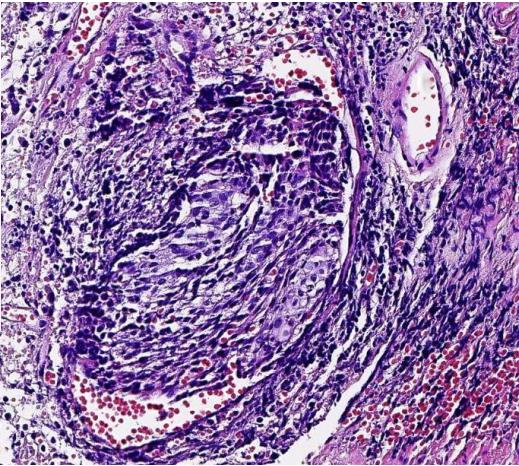

病变组织制成厚约数微米的切片,通常用苏木精·伊红染色(HE染色),或其他方法染色后,用光学显微镜观察其微细病变。

到目前为止,传统的HE染色组织学观察方法仍然是病理学诊断和研究最基本的方法,还没有其他方法能够取代。